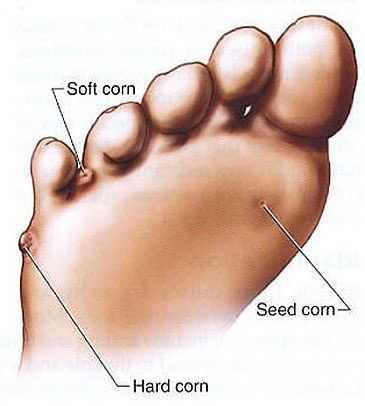

مسمار القدم : هو عبارة عن بروز لحمي أو نسيج يظهر على القدم، سبب ظهورها ضغط الجلد والعظام ضد الحذاء،وله الكثير من المُسميات الأخرى كالكالو أو عين السمكة أو مسمار الكيف، وهذا المرض من الأمراض التي تُصيب الجلد بشكل مُباشر.

يتكون مسمار القدم : من خلايا ميتة تتراكم على سطح الجلد وقد يبدو المسمار للناظر سطحياً إلّا أنّه عادة يكون على شكل قمع عميق في الجلد يحدث ألماً إذا ضغط عليه ..

يتكون مسمار القدم : من خلايا ميتة تتراكم على سطح الجلد وقد يبدو المسمار للناظر سطحياً إلّا أنّه عادة يكون على شكل قمع عميق في الجلد يحدث ألماً إذا ضغط عليه ..